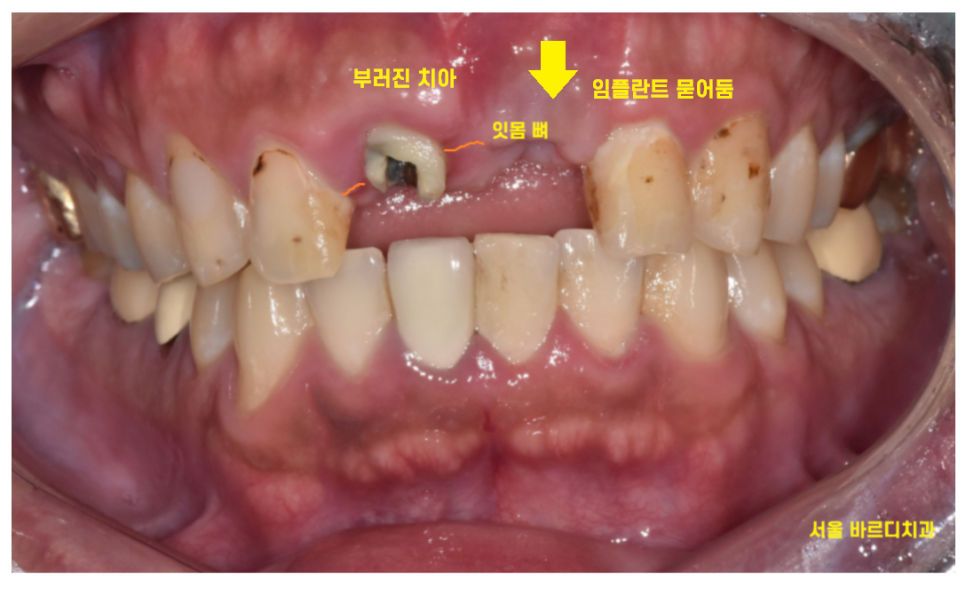

한눈에 봐도 치아가 많이 부러졌습니다.

안쪽에서 들여다보니

신경치료때 사용한 재료가 다 보일 정도로

부러졌습니다.

이런 이런

치료 받는 옆에 치아가 똑.. 부러져버렸네요

24.01.22

치아 1개가 또 부러졌네요.

잇몸 뼈 안쪽으로 뿌리만 남아있는 상황입니다.